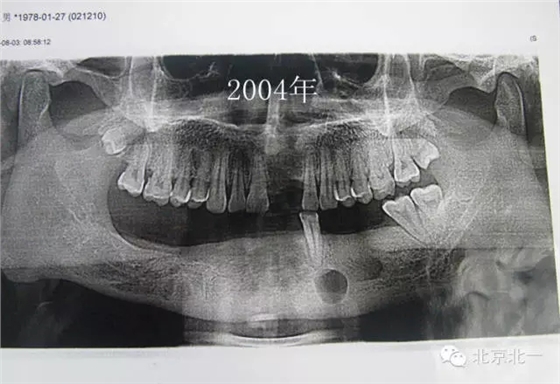

患者男,33歲,左下頜囊腫復(fù)發(fā)兩次就診。

圖一、初診時(shí)全景片